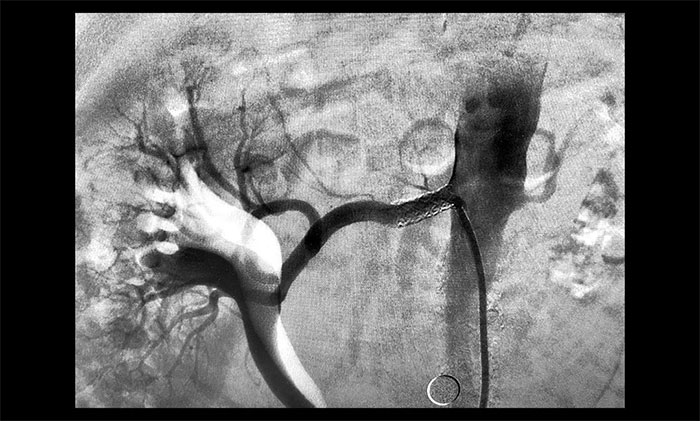

肾动脉位置较为特殊,要顺利完成支架置入手术,需要在分毫之间运作导丝完成操作、定位,十分考验手术医生的技术手法和临床经验。席刚明教授团队充分完善手术预案,迎难而上,于2023年12月14日为患者行右侧肾动脉支架置入手术。一系列精细的操作下,通过球囊扩张改善狭窄,再撤出球囊,将支架于狭窄段扩张释放……每一步都要既谨慎又到位,术中造影即可见狭窄明显改善。历时近一个小时,手术顺利完成。

▲ 支架置入后狭窄明显改善

术后,患者恢复情况良好,未出现明显并发症。长期困扰患者的高血压等症状得到缓解改善,于2023年12月25日,也就是手术后不到两周顺利出院。出院时测得其血压值为105/65 mmHg,降至理想水平。